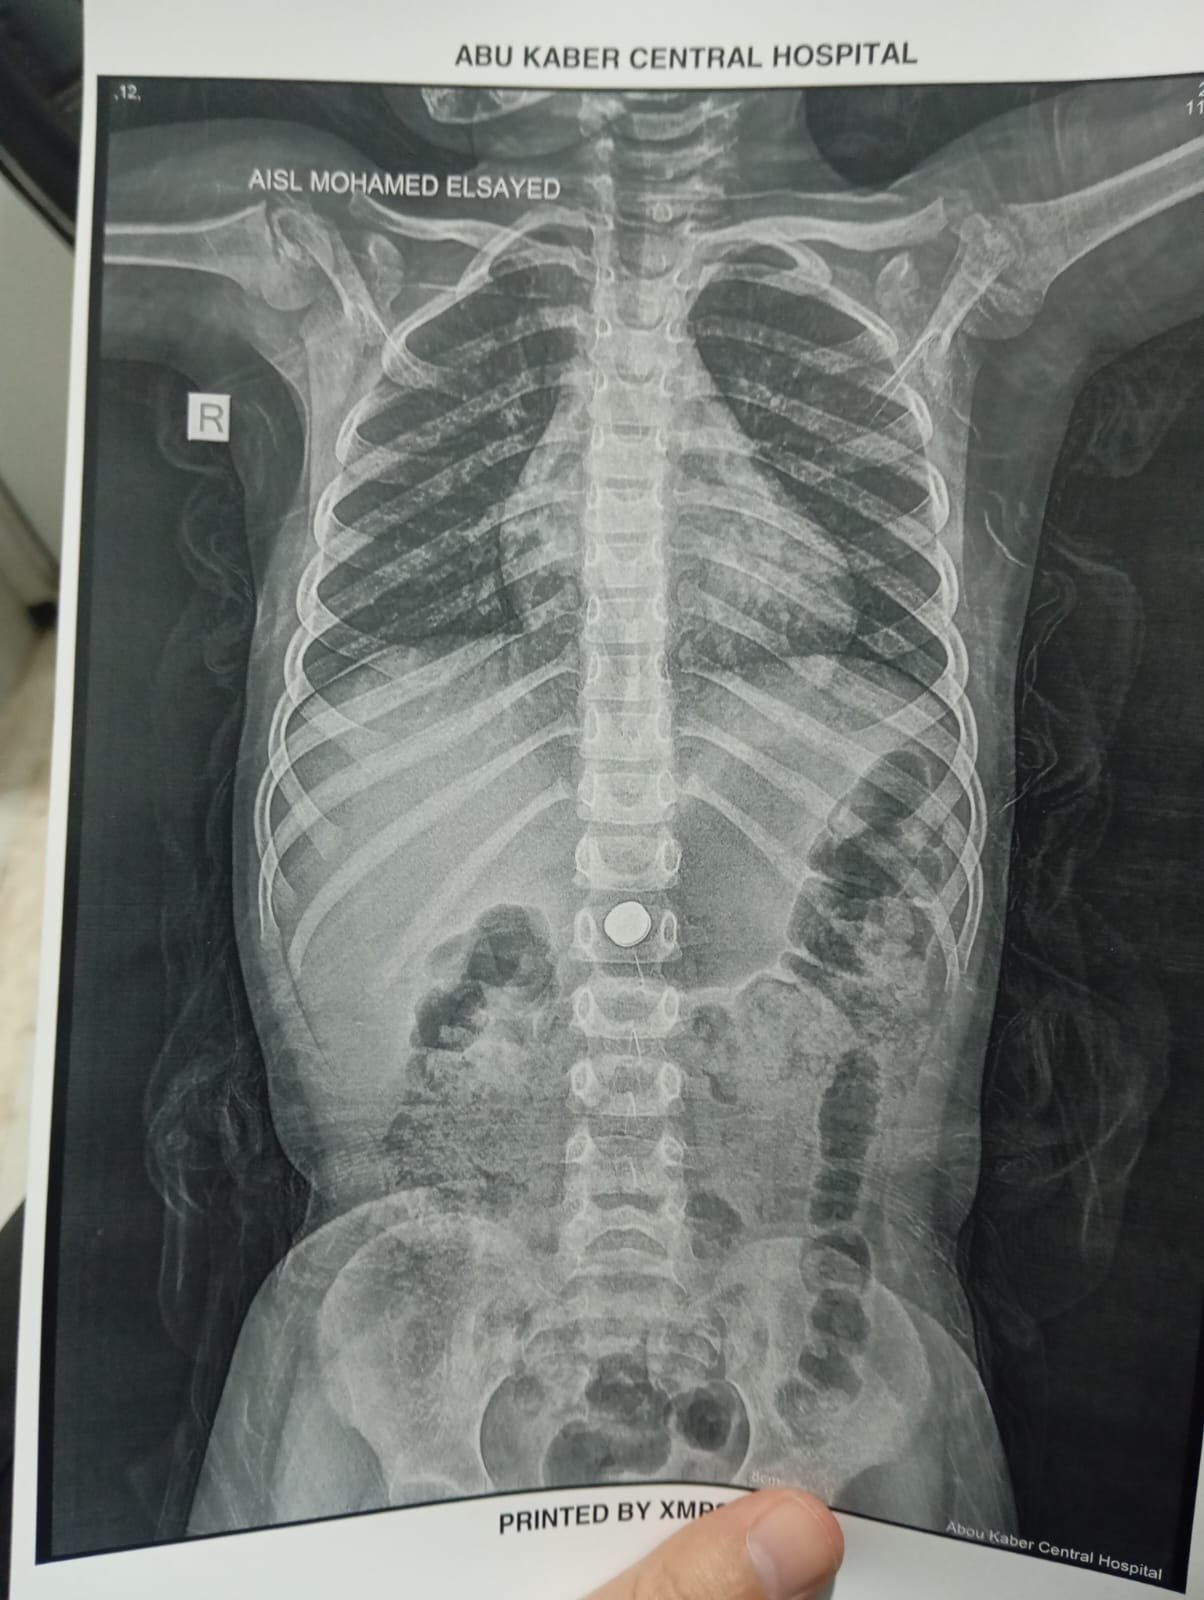

وأوضح الدكتور أحمد البيلي وكيل وزارة الصحة بالشرقية، أن الطفلة حضرت إلى قسم الاستقبال والطوارئ بالمستشفى بعد ابتلاع بطارية معدنية صغيرة، وهي من الحالات شديدة الخطورة التي قد تؤدي إلى حروق كيميائية عميقة بالمريء أو المعدة خلال وقت قصير، أو قد يصل الأمر إلى حدوث ثقوب أو نزيف حاد يهدد حياة الطفلة، نظراً لقدرة البطاريات على تفريغ شحنتها داخل الجسم خلال دقائق قليلة، مما استدعى سرعة التعامل الفوري مع الحالة وإجراء منظار ذات مهارة لها دون أي تأخير.

وأشار الأستاذ محمود عبدالفتاح مدير الإعلام والعلاقات العامة بالمديرية، إلى أنه فور استقبال الحالة، تم التنسيق الفوري من خلال مركز الخدمات الطارئة ١٣٧ بالمديرية، وتم تحويل الحالة إلى وحدة مناظير الجهاز الهضمي للأطفال، وإجراء كافة الفحوصات الطبية اللازمة لها، وإجراء منظار عاجل باستخدام التقنيات الحديثة، حيث نجح الفريق الطبي بفضل الله، في استخراج البطارية باستخدام شبكة المنظار، رغم صعوبة الحالة ووجود طعام داخل المعدة، وذلك مع الحفاظ على سلامة الأنسجة وعدم حدوث مضاعفات، وخرجت الطفلة بحالة عامة جيدة، وتحت الملاحظة الطبية للاطمئنان على استقرار حالتها.